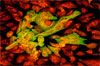

• Диагностика герпеса

Диагностика герпеса

Проблема заболеваний, вызванных вирусами простого герпеса (ВПГ) чрезвычайно актуальна. Инфицированность взрослого населения ВПГ приближается к 100%. Так в 15 летнем возрасте антитела к ВПГ-1